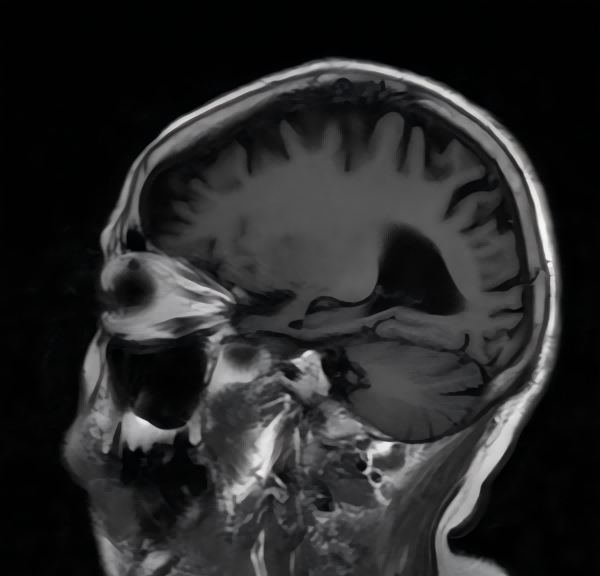

MRI具有无创、无辐射、空间分辨率高的独特优势,是评估阿尔茨海默病的最佳影像检查方法之一。它可以达到毫米级和亚毫米级的分辨率,精细地描绘大脑中神经结构的变化。

阿尔茨海默病最早影响的脑区之一是海马,这是参与学习和记忆的重要脑区。飞鱼影像的核磁检查能够智能化测量海马体积,观察内侧颞叶萎缩情况,发现早期、轻微的大脑变化。

MRI可以帮助医生排除其他疾病造成的痴呆,如脑肿瘤、脑积水等。

飞鱼影像采用多模块先进的MRI技术为阿尔茨海默病评估提供全面信息:结构磁共振(sMRI)可测量大脑皮层的体积和厚度来反映结构变化;弥散张量成像(DTI)能有效观察和追踪脑白质纤维束,直接从微观水平反映神经元功能的改变;静息态功能磁共振(r-fMRI)可以探测到局部脑区神经元活动情况。